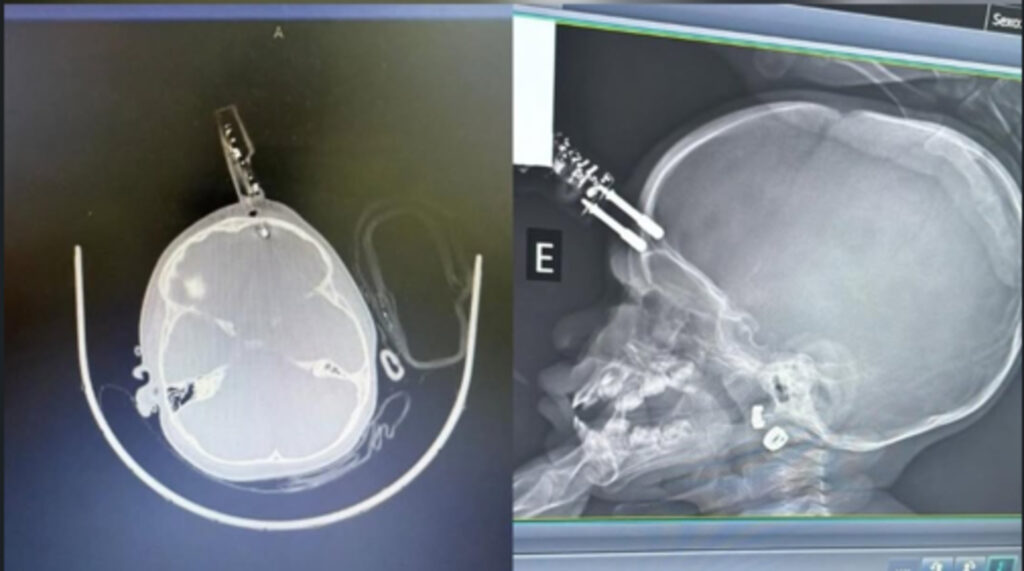

Menina que teve carregador de celular cravado na testa recebe alta